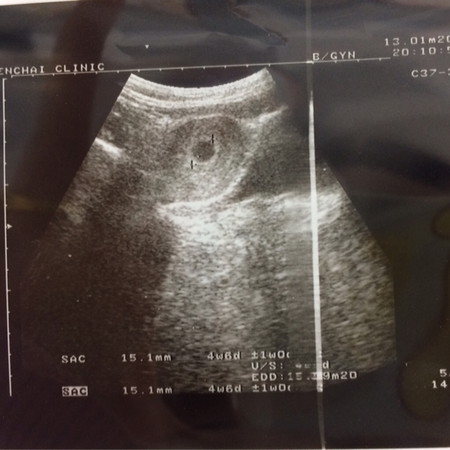

บ้านนี้กำหนดคลอด 15 ก.ย.63 ❣️